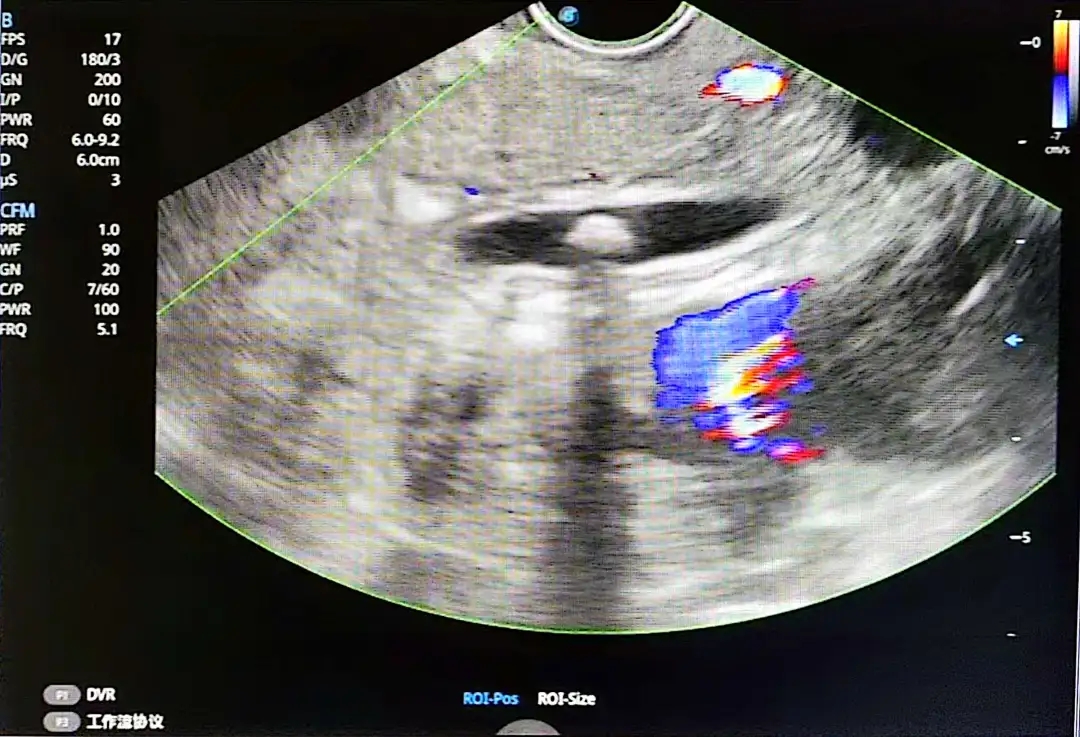

消化内科立即启动了应急方案:安排超声内镜(EUS)检查。这是目前诊断微小胆胰病变的“金睛火眼”,能发现CT和MRI难以捕捉的病灶。

检查室内,带有高清超声探头的特殊内镜(超声胃镜)缓缓进入周同学的十二指肠。屏幕上立即呈现出“关键证据”:胆总管下端一颗直径约6.8mm的结石卡在胆总管下段!这正是导致他腹部剧痛和黄疸的元凶。

超声内镜为何能发现CT“漏诊”的结石?

近距离扫描:探头经十二指肠紧贴胆胰区域,避免腹壁脂肪和肠道气体的干扰。

高频成像:7.5-12MHz的高频超声波能分辨毫米级的微小病变。

立体观察:可多角度显示结石与胆管壁的关系,判断是否嵌顿。

研究证实:超声内镜对胆总管结石的检出率超过90%,对CT阴性患者的诊断贡献率达82.6%。病因终于明确!